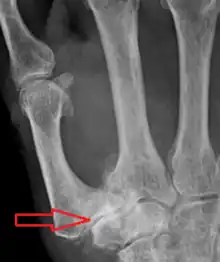

Stage 4 trapeziometacarpal osteoarthritis, with major subluxation of the joint.

Stage 4:

• Narrow joint space

• Concomitant scaphotrapezial arthritis

Diagnosis

TMC OA is diagnosed based on symptoms and signs.[8] Radiographs can confirm the diagnosis and the severity of TMC OA. Other diagnoses in this region include scaphotrapezial trapezoid arthritis and first dorsal compartment tendinopathy (De Quervain syndrome) although these are usually easy to distinguish.